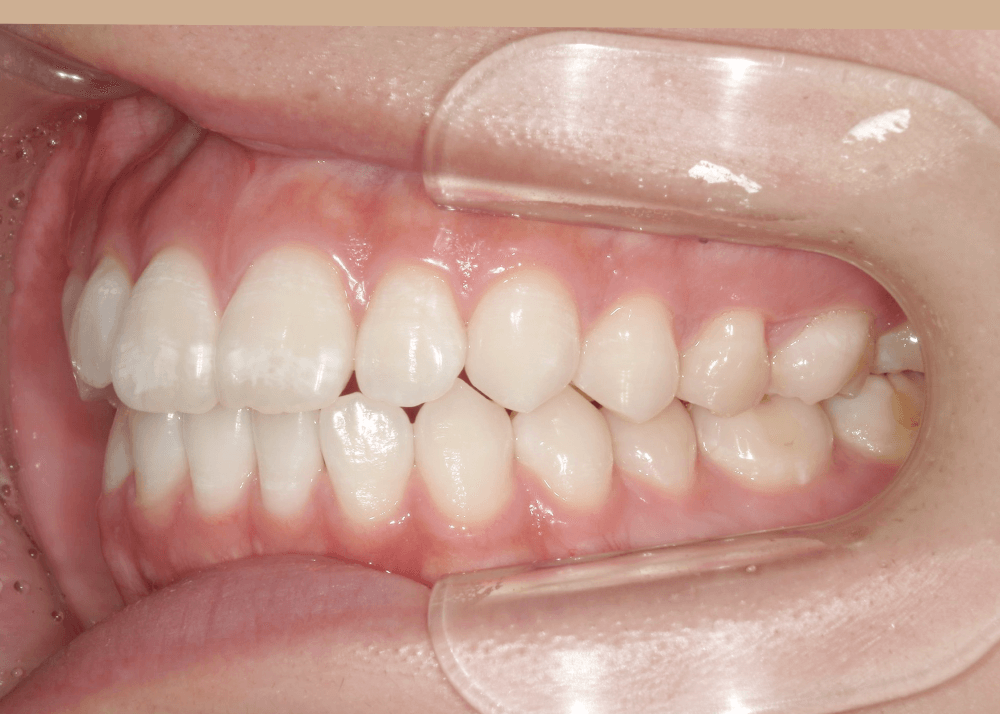

装置についてーハーフリンガル矯正ー

装置は、上あごは裏側、下あごは表側にワイヤー装置を装着する「ハーフリンガル矯正」を選択しました。

笑った際に目立ちやすい上あごの装置を裏側にすることで、審美性に配慮しながら治療を進めています。

治療後は、気にされていた「口ゴボ(口元の突出感)」が改善され、自然でバランスの良い口元になりました。

隙間のあった前歯も、しっかり噛み合うようになっています。

治療後(32か月)